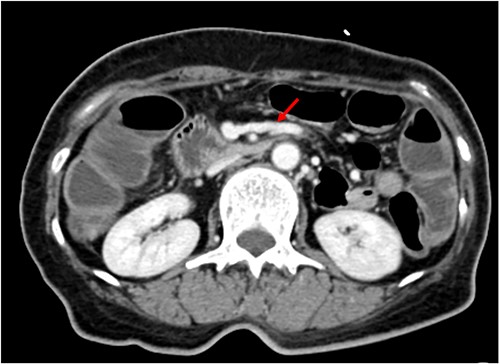

We made an incision avoiding the tumor. The patient’s abdominal cavity showed overall adhesion due to previous surgery. We found tumor invading or being adherent to the duodenum and superior mesenteric vein (Fig. 3). We thought that superior mesentery vein (SMV) collapsed due to compression, but it was identified completely occluded due to invasion. We also found that jejunal first branch was very dilated due to obstruction (Fig. 4). We performed completion right hemicolectomy with duodenal segmental resection, SMV resection and anastomosis (Fig. 5). Anterior resection was performed for the accompanying sigmoid colon cancer.

Tumor invaded or was adherent to the duodenum and superior mesenteric vein.

Dilated jejunal first branch of superior mesenteric vein (red arrow).